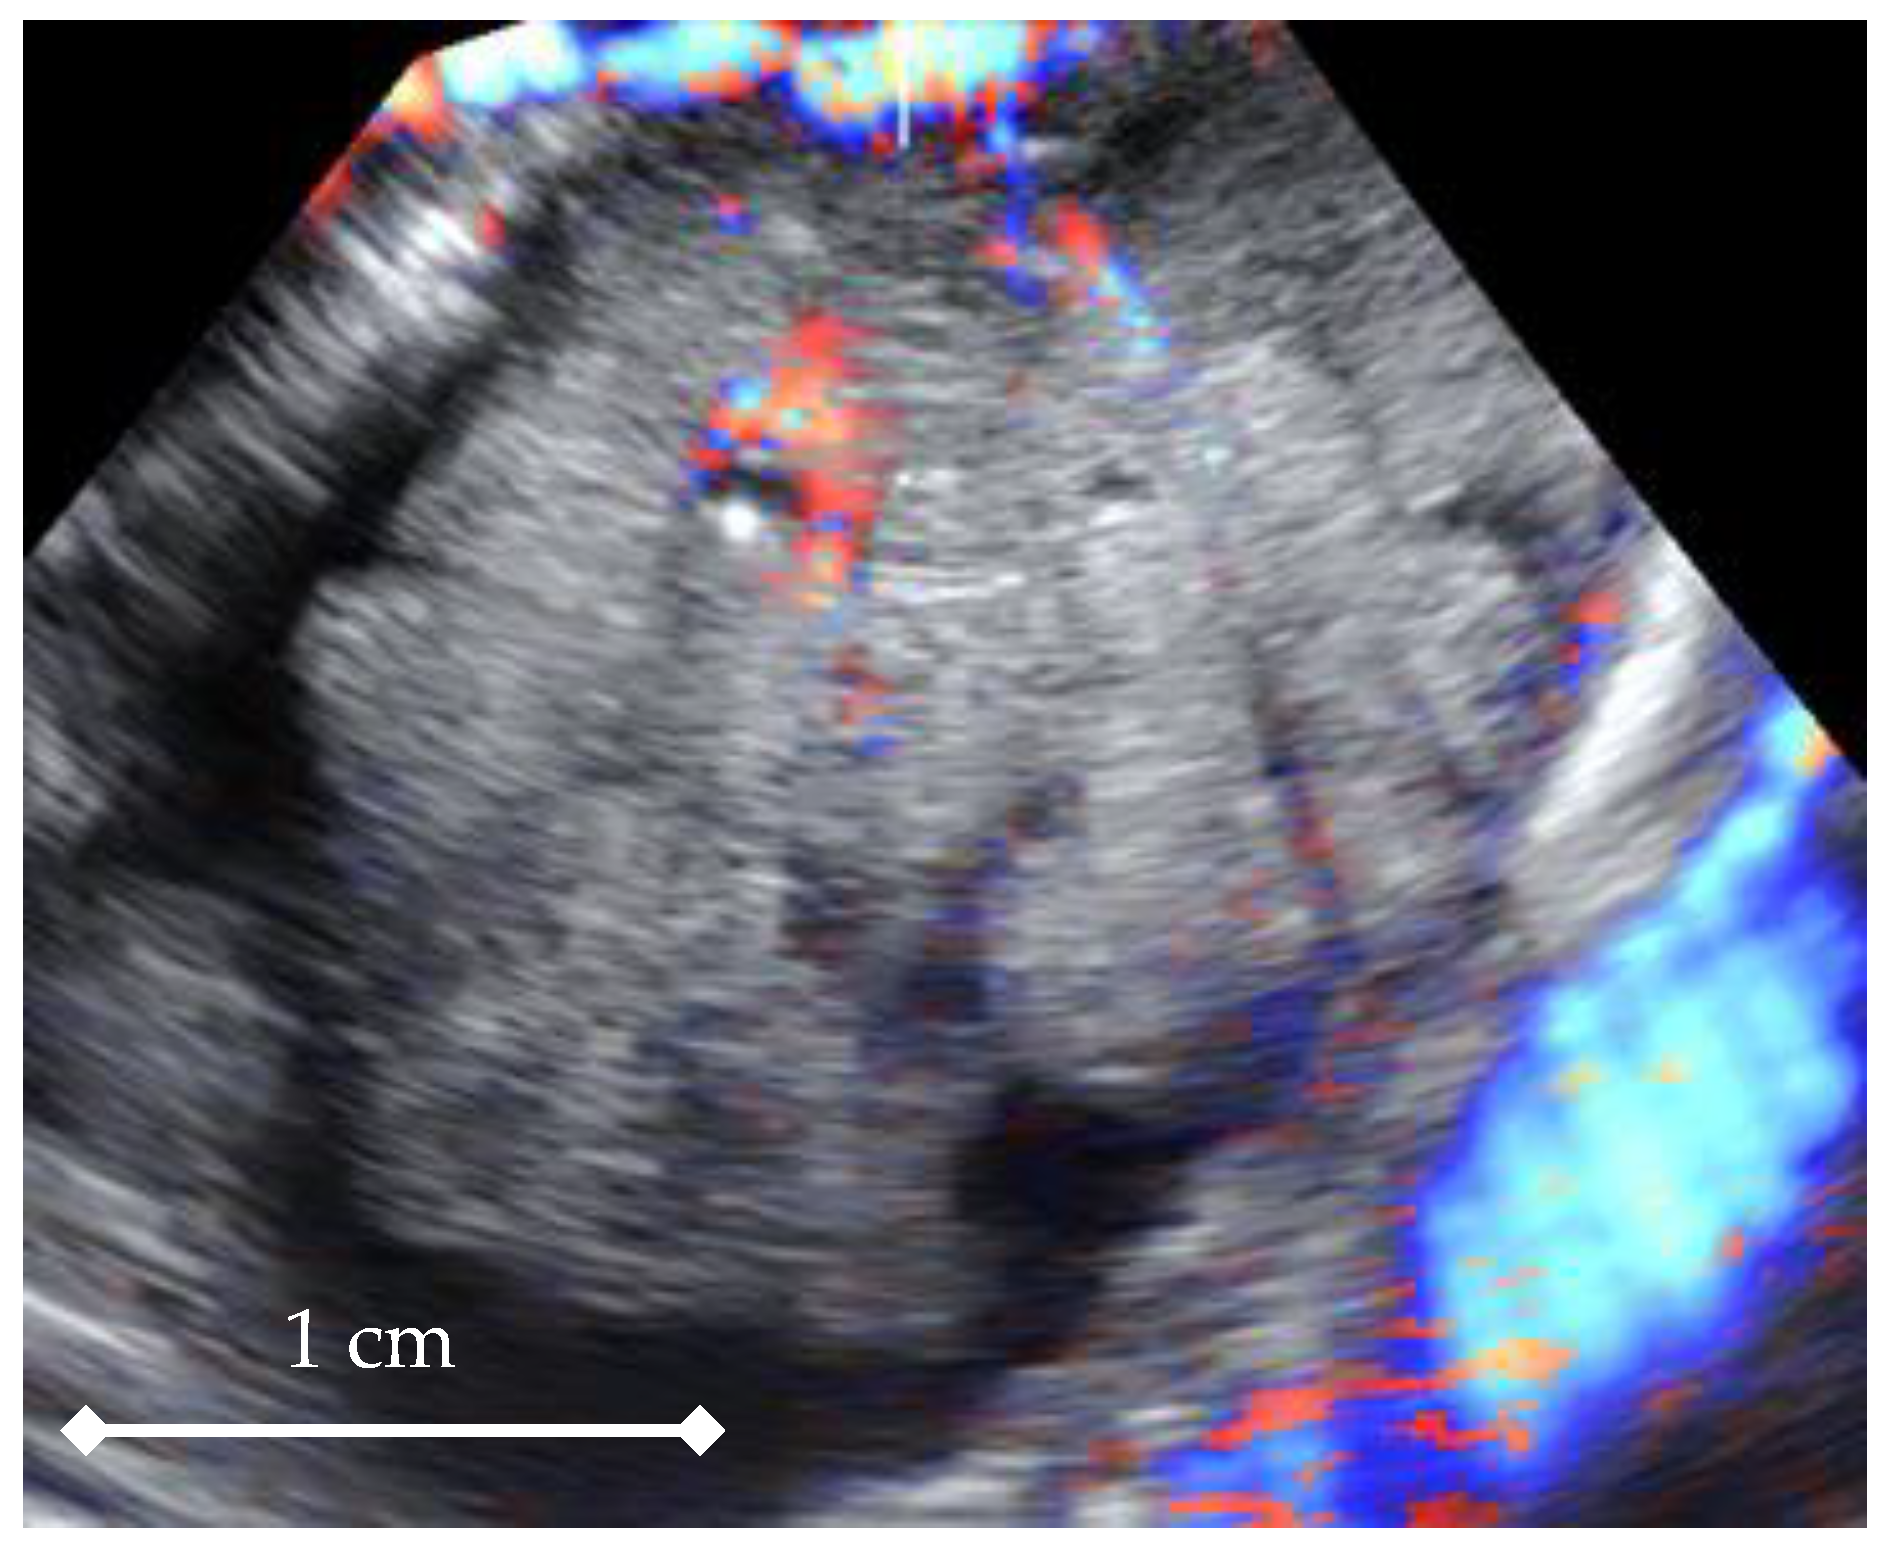

4D Doppler Ultrasound in High Grade Serous Ovarian Cancer Vascularity Evaluation—Preliminary Study